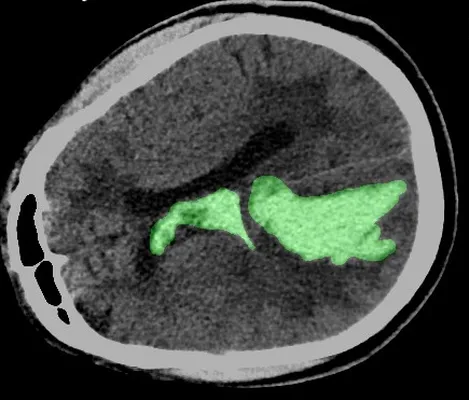

passion for innovation of AI in Medical Images, drove me to

focus my thesis on developing AI-assisted software for

classifying and segmenting intracerebral hemorrhage.